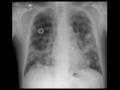

Lung Metastases on Chest X-ray

Chest x-ray in a patient with colon cancer demonstrates extensive bilateral lung metastases. A central venous catheter is also noted on the right.